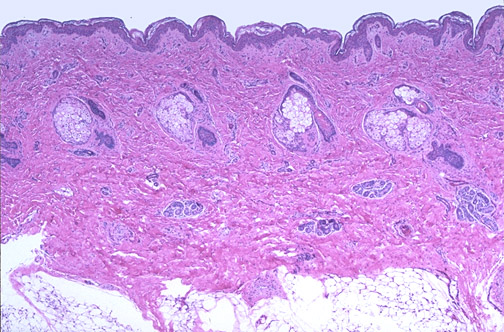

| Normal baby skin is shown here at low magnification. The keratinizing squamous epithelium is supported by the papillary dermis. There are hair follicles and accompanying adnexae including sebaceous glands and sweat glands. Beneath the reticular dermis is the subcutaneous adipose tissue. |